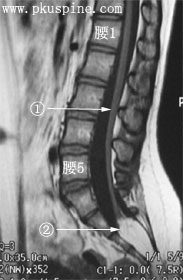

3 椎脊髓血管性病變:脊髓血管畸形,髓周動靜脈瘺,硬脊膜動靜脈瘺,海綿狀血管畸形,脊髓動脈瘤等.

4 柱疾病:頸椎病,椎管狹窄,後縱韌帶骨化,椎間盤突出等.